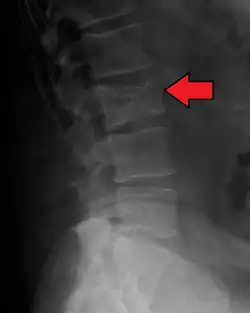

The diagnostic examination of a person with suspected multiple myeloma typically includes a skeletal survey. This is a series of X-rays of the skull, axial skeleton, and proximal long bones. Myeloma activity sometimes appears as "lytic lesions" (with local disappearance of normal bone due to resorption) or as "punched-out lesions" on the skull X-ray ("raindrop skull"). Lesions may also be sclerotic, which is seen as radiodense.[76] Overall, the radiodensity of myeloma is between −30 and 120 Hounsfield units (HU).[77] Magnetic resonance imaging is more sensitive than simple X-rays in the detection of lytic lesions. An MRI may supersede a skeletal survey, especially when vertebral disease is suspected. Occasionally, a CT scan is performed to measure the size of soft-tissue plasmacytomas. Nuclear Medicine Bone scans are typically not of any additional value in the workup of people with myeloma (no new bone formation; lytic lesions not well visualized on nuclear bone scan).

Skull X-ray showing multiple lucencies due to multiple myeloma -

Pathological fracture of the lumbar spine due to multiple myeloma -